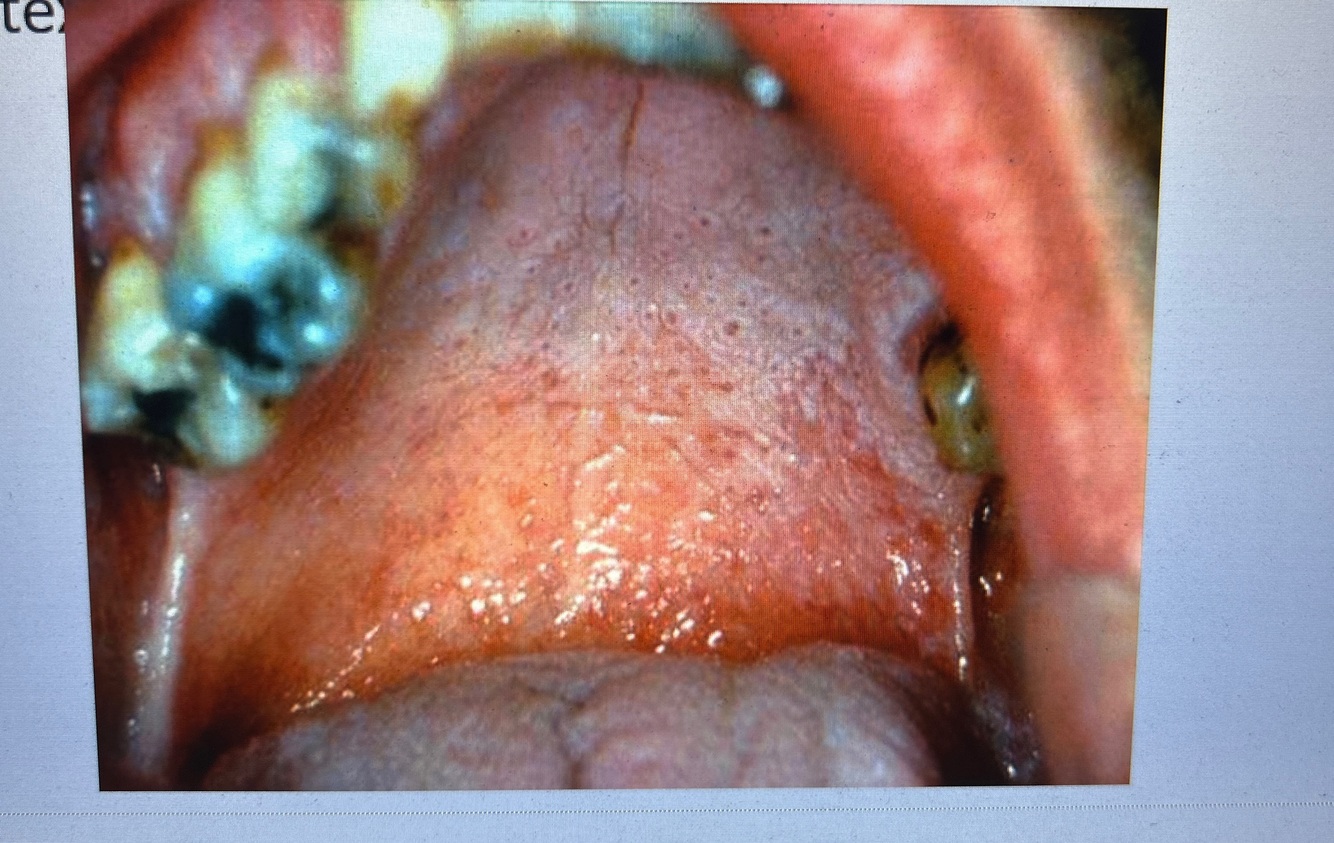

Q

What is this

A

Smoker’s keratosis